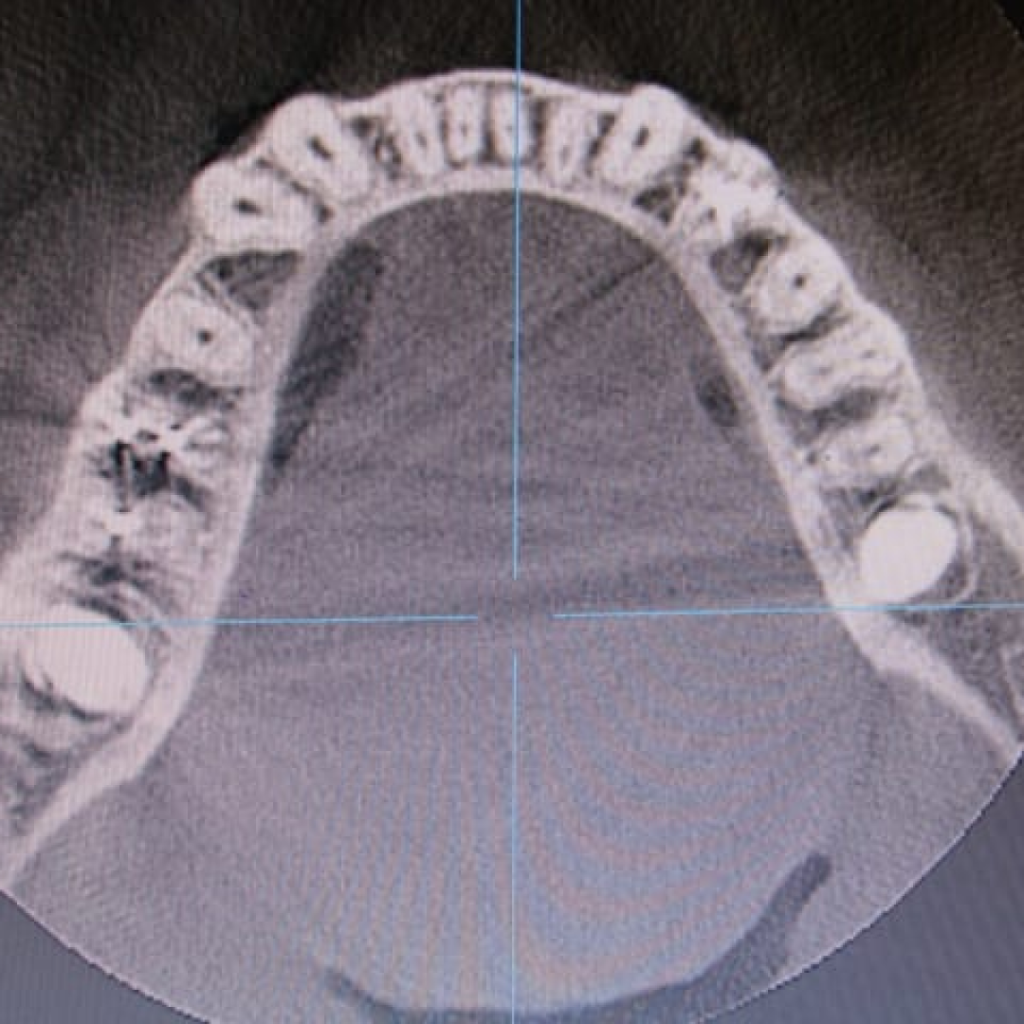

Пациентке по терапевтическим показаниям были удалены зубы 37 и 47.

Особенности анатомии зубов после удаления составили:

- сросшиеся медиальный и дистальный корень

- отсутствие межкорневой перегородки

- диаметр лунок более 11 мм